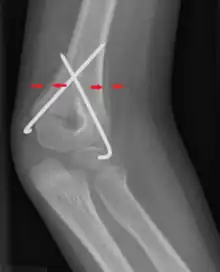

| Periosteal reaction on a healing supracondylar fracture | |

A periosteal reaction is the formation of new bone in response to injury or other stimuli of the periosteum surrounding the bone.[1] It is most often identified on X-ray films of the bones.